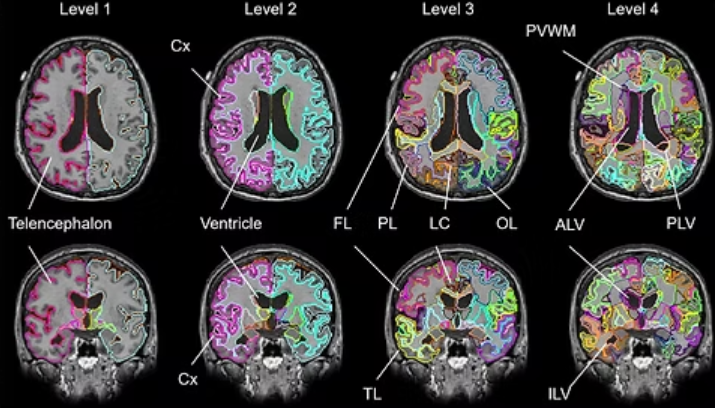

Mvision health(エムビジョンヘルス)は、ジョンスホプキンス大学特許によるMRIのAI解析システムとビッグデータを用い脳を解析。

脳の「健康度」「老化の進行度」について経時的なモニタリングを可能とします。

どんな解析をするの?